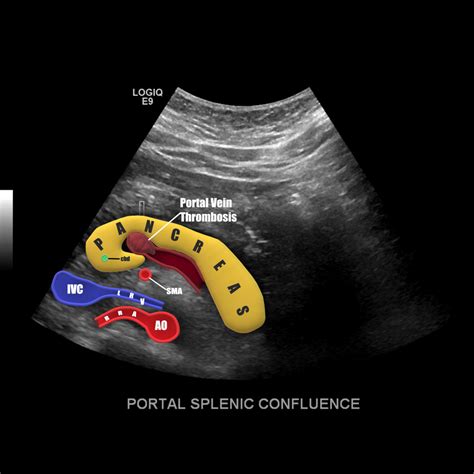

• Imaging Studies: Ultrasound, CT scan, or MRI can provide detailed images of the spleen and help diagnose conditions such as splenomegaly or splenic rupture.

• Imaging Studies: Ultrasound, CT scan, MRI, or endoscopic ultrasound can provide detailed images of the pancreas and help diagnose conditions such as pancreatic cancer or pancreatitis.

• pancreas and splenic vein